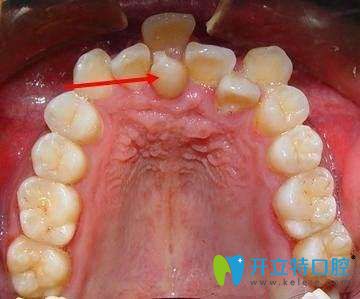

2、影響牙周組織健康及口腔衛(wèi)生。牙列不齊會(huì)使口腔菌斑易于附著,牙刷也難以接觸,導(dǎo)致牙齦出血、腫脹、口腔異味等癥狀;久而久之還會(huì)累及牙槽骨,出現(xiàn)牙齒松動(dòng)。